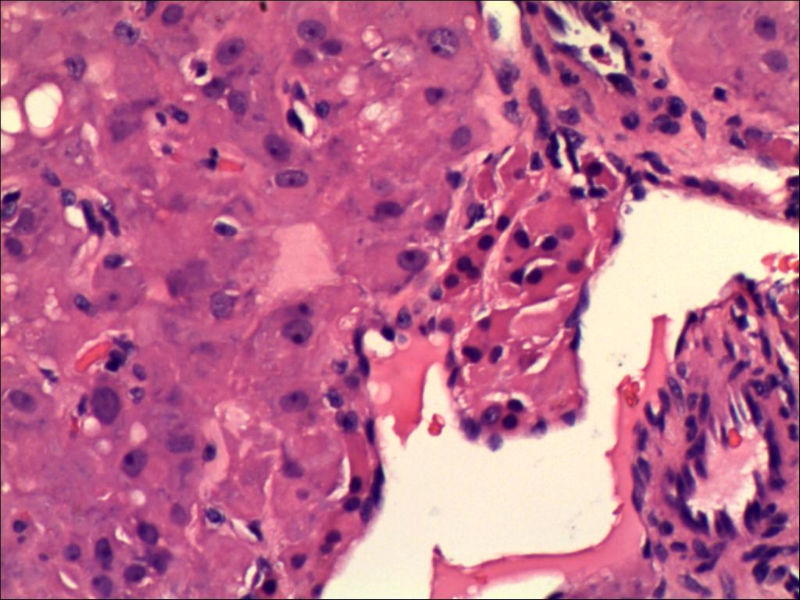

女,27岁,送检右侧卵巢肿物(另外还送检左侧卵巢肿物,大体及镜下显示为畸胎瘤),卵圆形,大小2×1×1cm,似有包膜。卵巢肿物图1

卵巢畸胎瘤中正常卵巢的黄体组织,铺砖样排列,胞浆宽大,较典型。

不好意思,可能是我没说清楚,患者对侧卵巢是畸胎瘤,不是同一侧的,我初步考虑门细胞瘤,图21,22,24,25,26中央的一些细胞是不是很像门细胞

谢谢大家的回答和解疑,忘记一个重要的病史,就是该女性为产妇。但是妊娠黄体瘤与类固醇细胞瘤怎么鉴别呢

那应该是妊娠黄体/黄体瘤,类固醇细胞瘤有嗜酸细胞和组织细胞样细胞两种,此例显然不是。